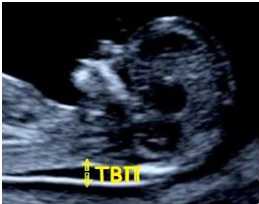

- Измерение толщины воротникового пространства (сокращенно - ТВП)

Каковы нормальные значения толщины воротникового пространства (ТВП)?

| Нижняя граница нормы | Верхняя граница нормы | Среднее значение | |

| 10 недель | 0,8 | 2,2 | 1,5 |

| 11 недель | 0,8 | 2,2 | 1,6 |

| 12 недель | 0,7 | 2,5 | 1,7 |

| 13 недель | 0,7 | 2,8 | 1,7 |

| 14 недель | 0,8 | 2,8 | 1,8 |

О чем свидетельствует увеличение ТВП?

Увеличение толщины воротникового пространства - один из признаков хромосомных аномалий, чаще всего данный маркер характерен для синдрома Дауна, за счет скопления жидкости в этой области. Однако, следует знать, что измерение ТВП должна проводиться при определенном положении эмбриона (он не должен излишне сгибать или разгибать голову).